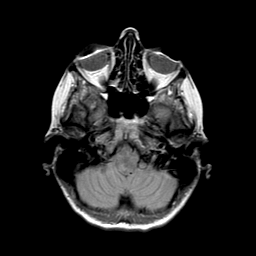

Metastatic bronchogenic carcinoma: proton density-weighted MR -- Slice #3

[Home][Help][Clinical] Slice 3